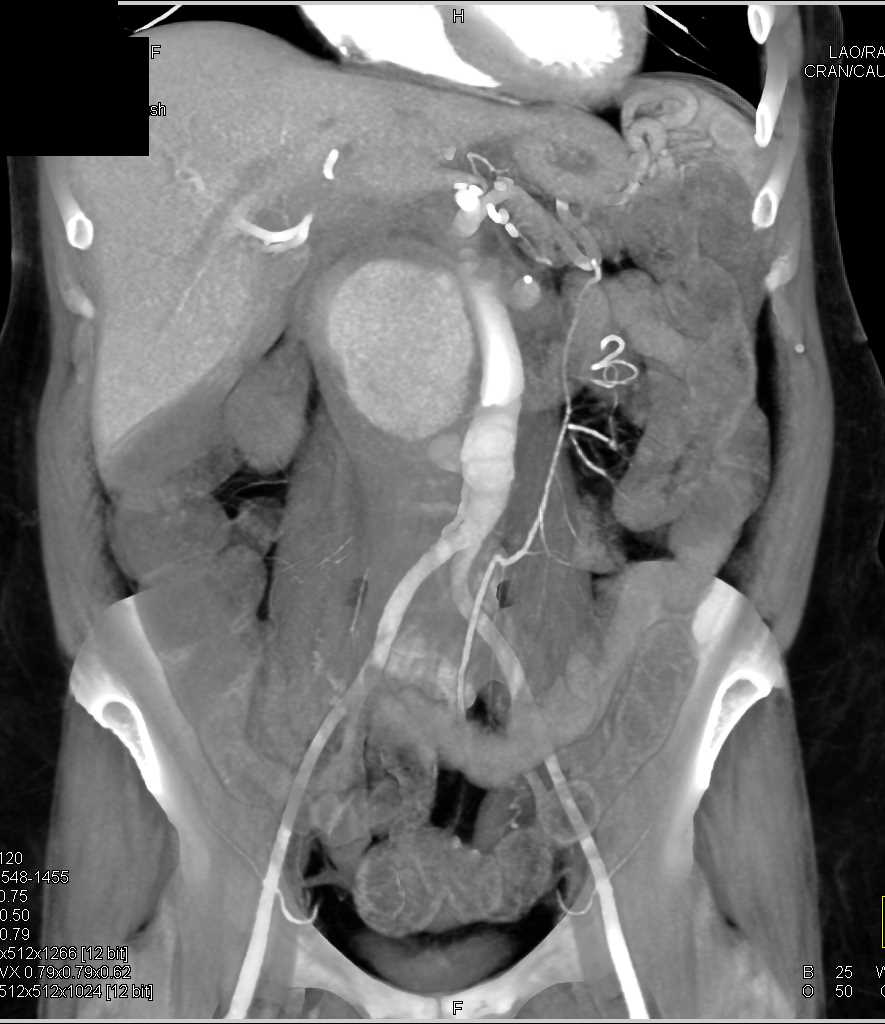

Occlusion Left Common Iliac Artery